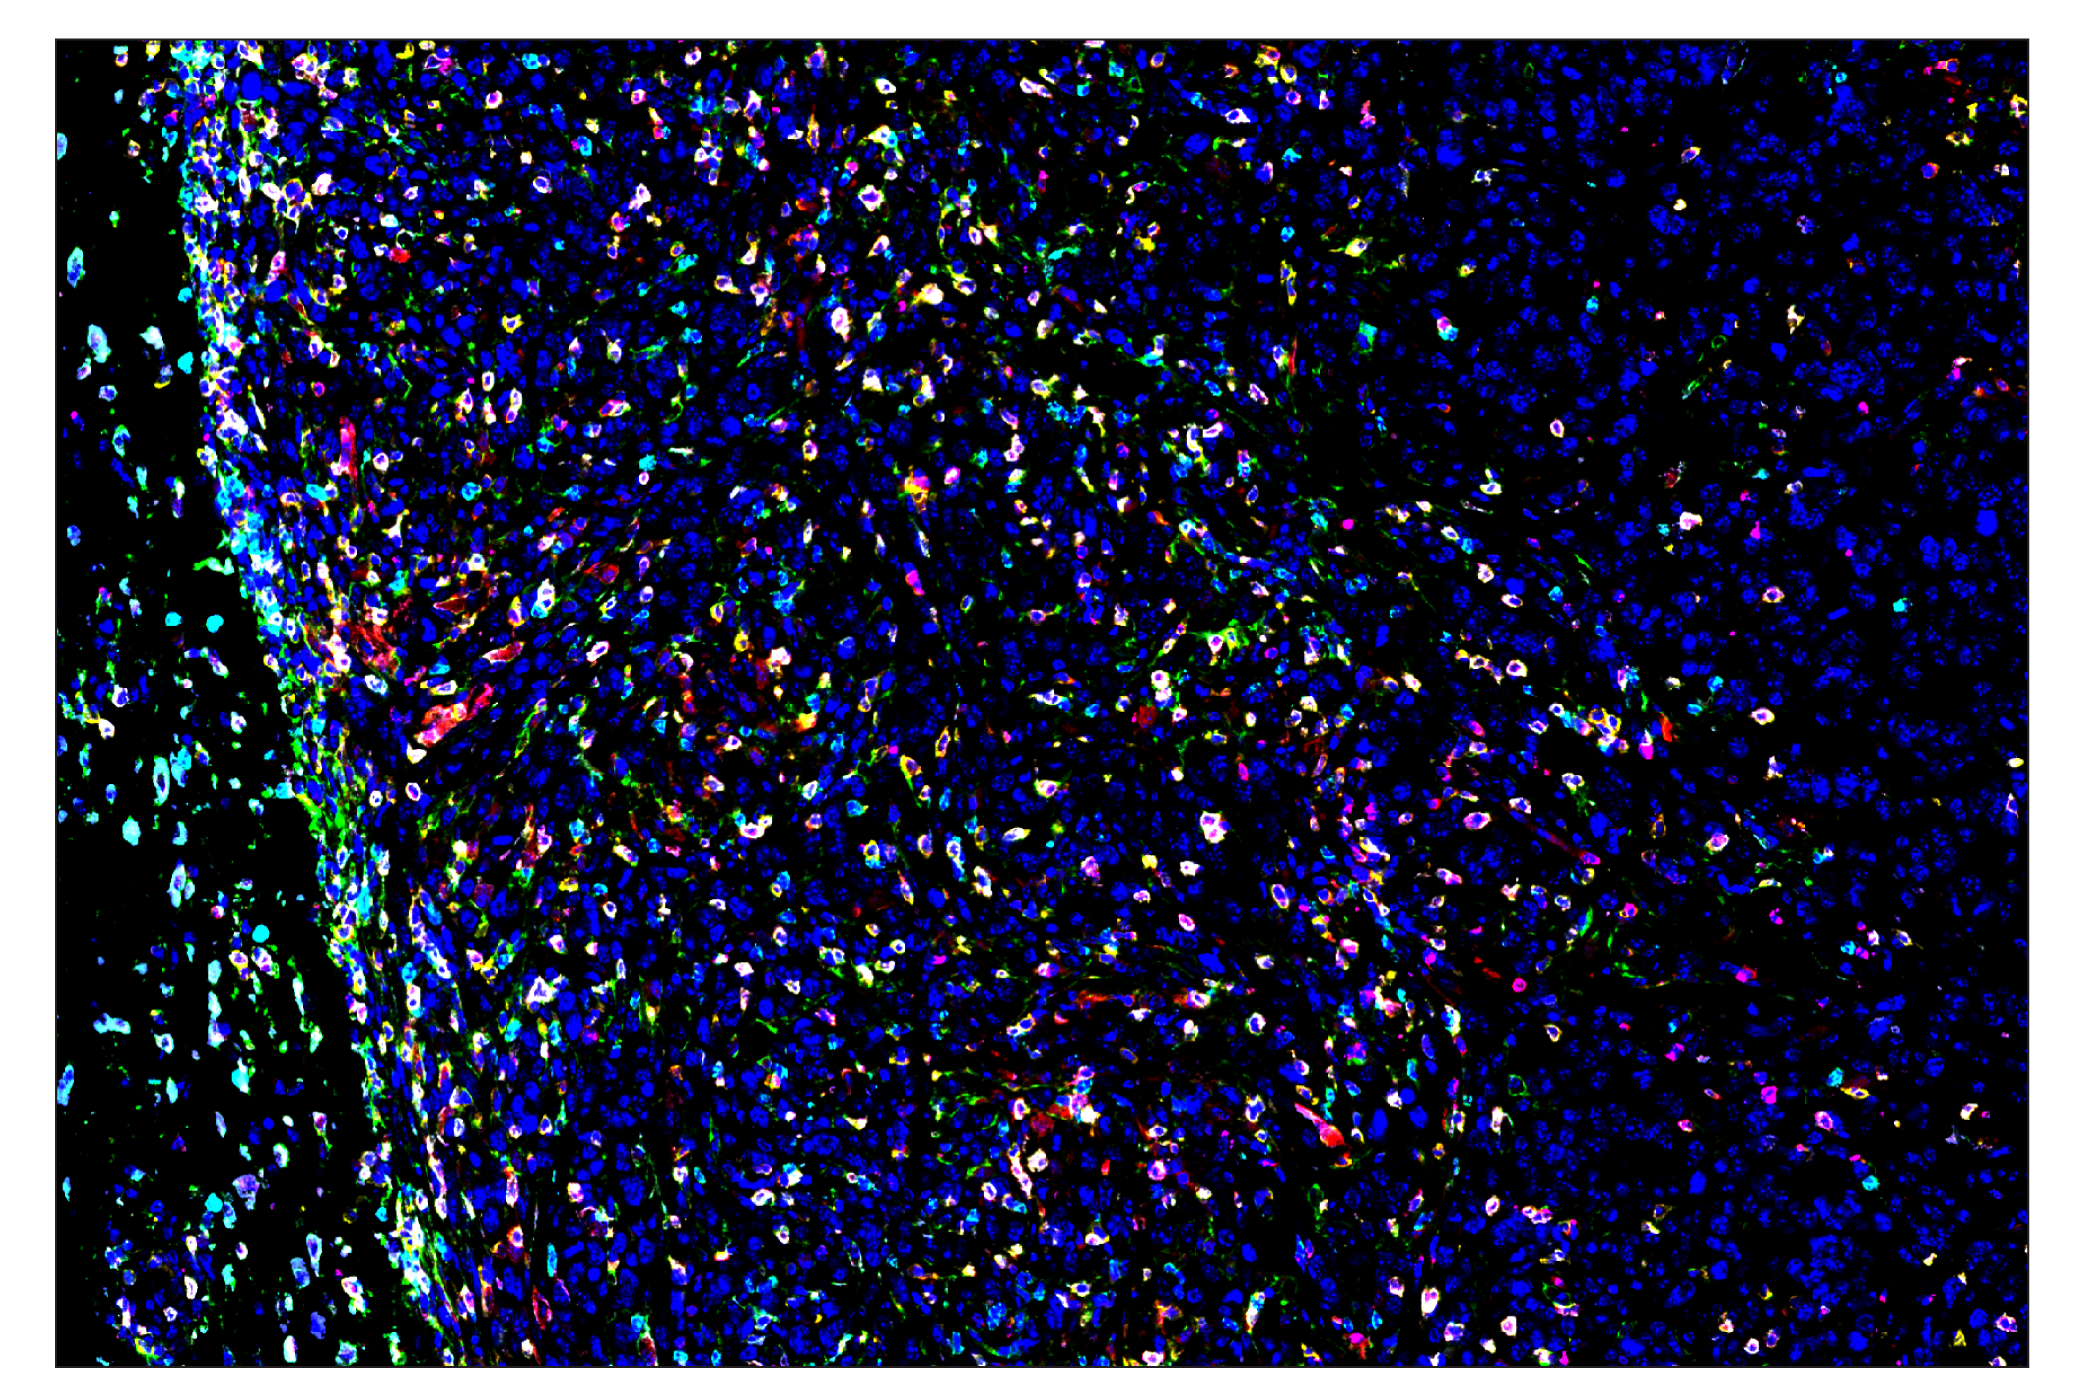

ASC/TMS1 (D2W8U) & CO-0226-594 SignalStar® Oligo-Antibody Pair #59906

SignalStar multiplex immunohistochemistry (IHC) is an advanced technology for labeling multiple proteins simultaneously in tissue samples using specific primary antibodies and fluorescent detection reagents. This technology offers accuracy and reliability in visualizing and analyzing protein expression while maintaining spatial context and tissue architecture.

SignalStar Oligo-Antibody Pairs are compatible with the SignalStar Multiplex IHC Buffer Kits for use in fluorescent multiplex imaging experiments. This product includes the oligo-conjugated antibodies and complementary oligos required for labeling your target protein on up to 10 slides. SignalStar Multiplex IHC Buffer Kits are required to amplify and image the target signal. Multiple oligo-antibody pairs can be conveniently combined into a multiplex panel using the SignalStar Multiplex IHC Panel Builder. SignalStar Multiplex IHC Kits & Reagents are not compatible with all of Cell Signaling Technology® products and protocols that are recommended for use in immunohistochemical assays.